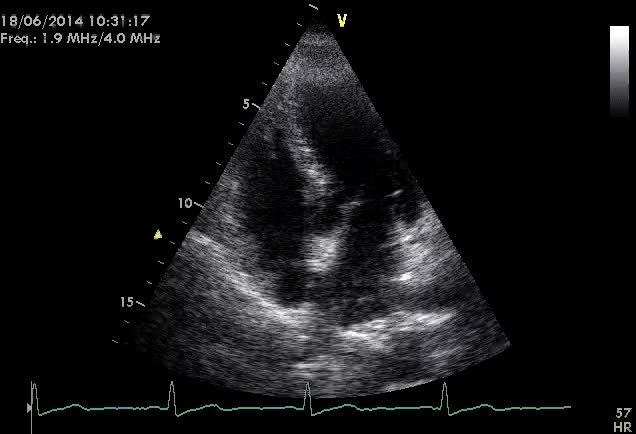

Titolo:

Epatocarcinoma

Autore:

Anna Maltagliati